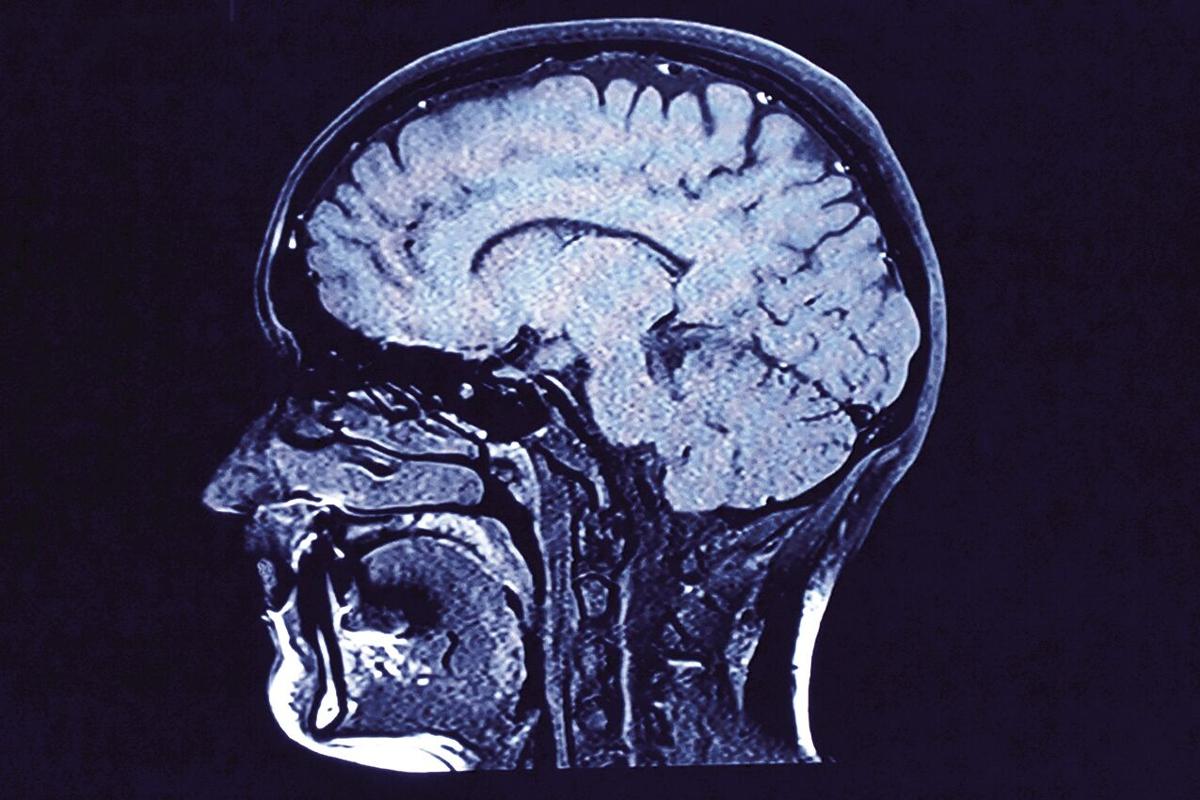

Cerebral angiography: Healthline says a cerebral angiography involves injecting a contrast medium into your blood so that imaging will clearly show blood vessels in the brain, which can help identify any blockages or bleeds.